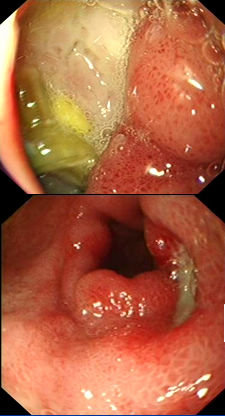

消化性溃疡分为活动期(active stage,A期)、愈合期(healing stage,H期)、瘢痕期(scarring stage,S期)

A1期:底厚苔,可污秽,可超出溃疡边缘,可有出血点或血痂附着,周围粘膜隆起呈堤状,充血、水肿,糜烂,明显炎症表现。

A2期:溃疡周边炎症水肿明显减轻,白苔清洁,边界鲜明,边缘开始呈现红色的再生上皮,开始出现皱襞集中现象。

H1期:溃疡缩小、变浅,白苔边缘光滑,周边水肿消失,边缘再生上皮明显,呈红色栅状,皱襞集中到达溃疡边缘。

H2期:溃疡明显缩小,但尚存在,白苔变薄,再生上皮范围加宽。

S1期:粘膜缺损已完全由再生上皮覆盖,再生上皮发红呈栅状,向心性发射排列皱襞平滑向中心集中,又称红色瘢痕期。

S2期:再生上皮增厚,红色消失,与周围粘膜大体相同,皱襞集中不明显,但可见粘膜集中像,又称白色瘢痕期。